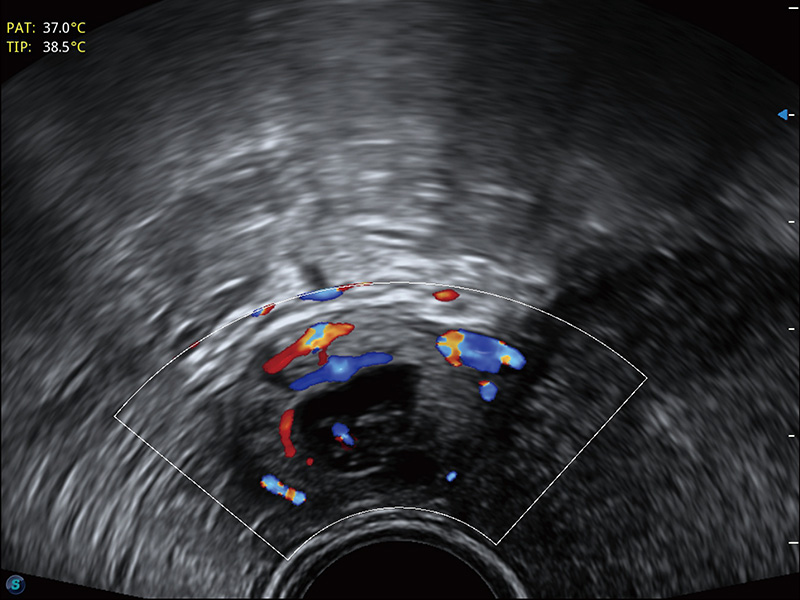

临床图

宫外孕血流

输卵管间质部妊娠